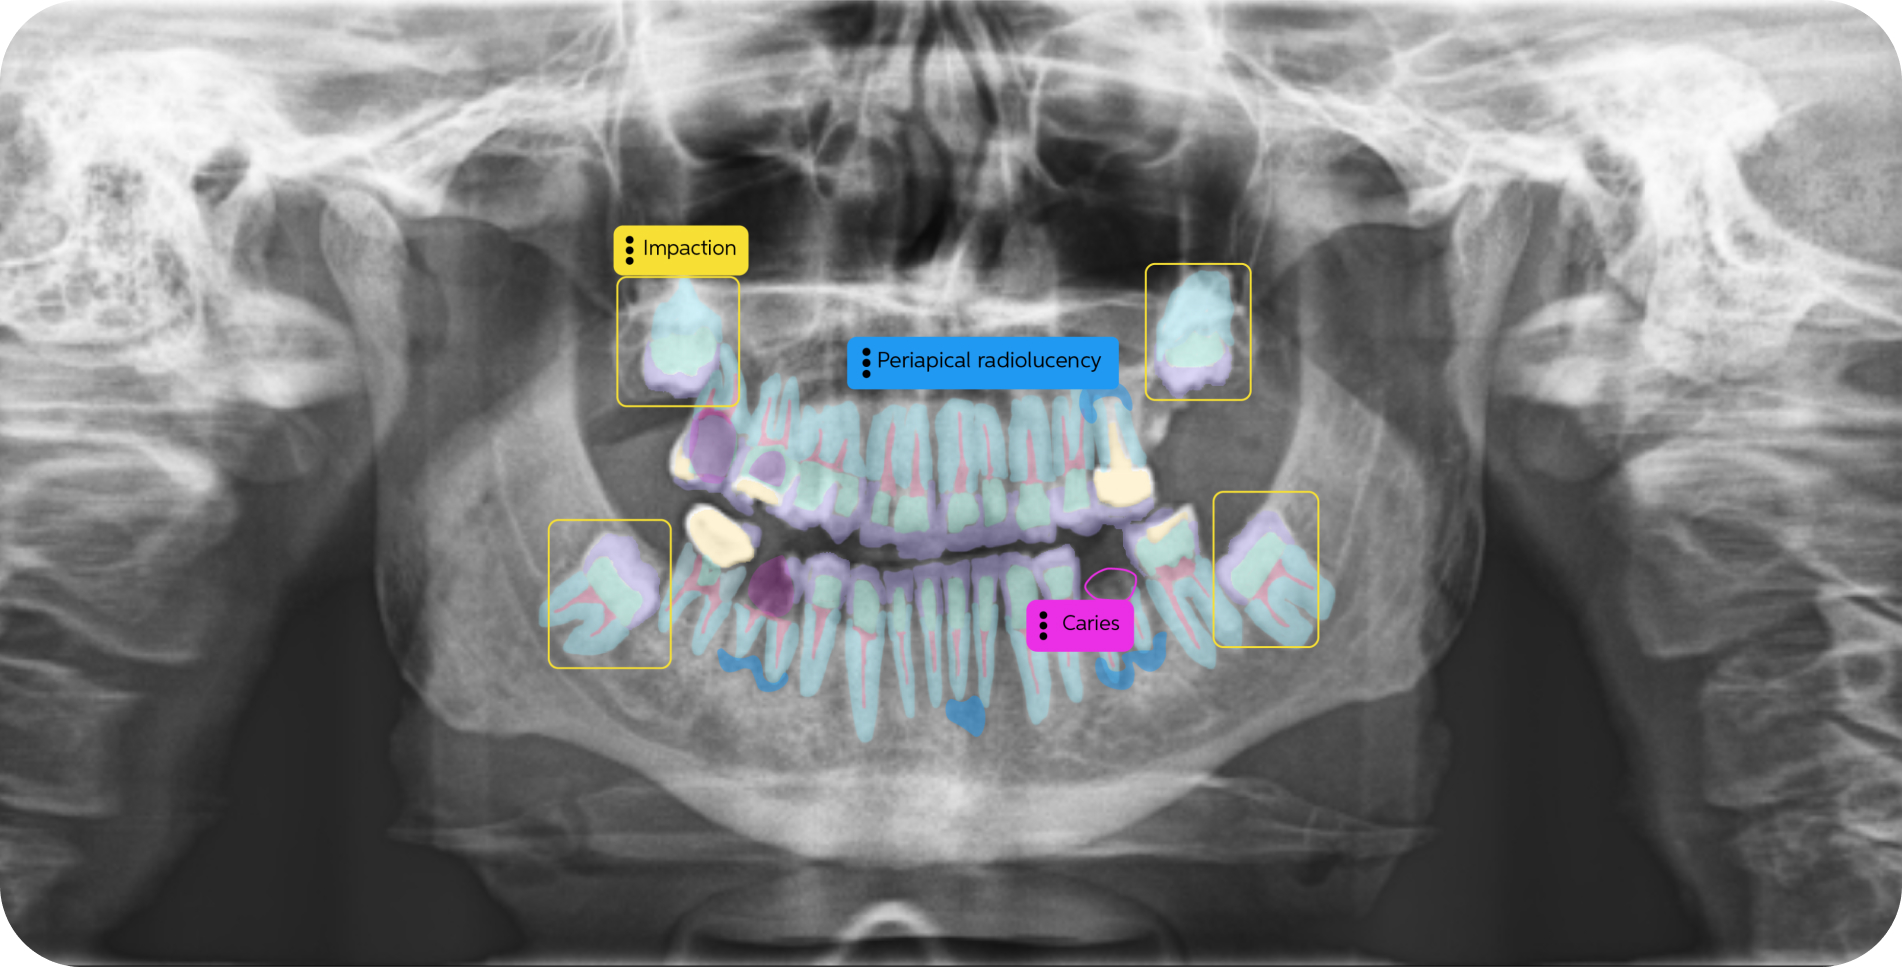

Pearl’s AI is trained on world's largest collection dental x-rays to detect a greater range of pathologies, existing restorations and natural anatomy than any solution of its kind, enabling 37% more accurate x-ray evaluations.

Color-coded detections, educational tooth part maps and quantitative results give patients an objective, clear and data-based foundation for trust in your findings––trust that boosts case acceptance by 24% on average.